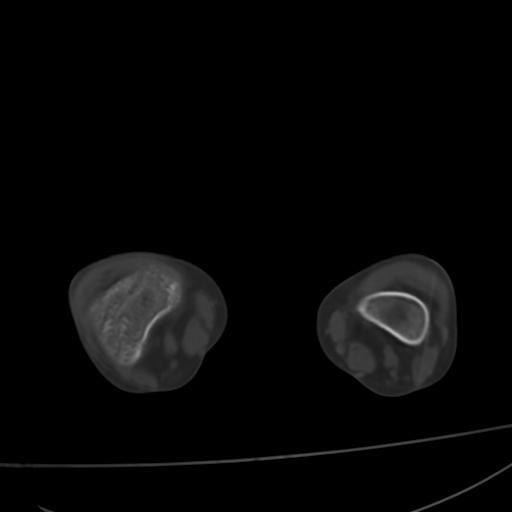

标题: PED0940:M12Y,左股骨下端酸痛畸形 [打印本页]

标题: PED0940:M12Y,左股骨下端酸痛畸形

12岁男孩,左膝关节肿痛8年,近月明显

内生骨软骨瘤?

血友性关节病?